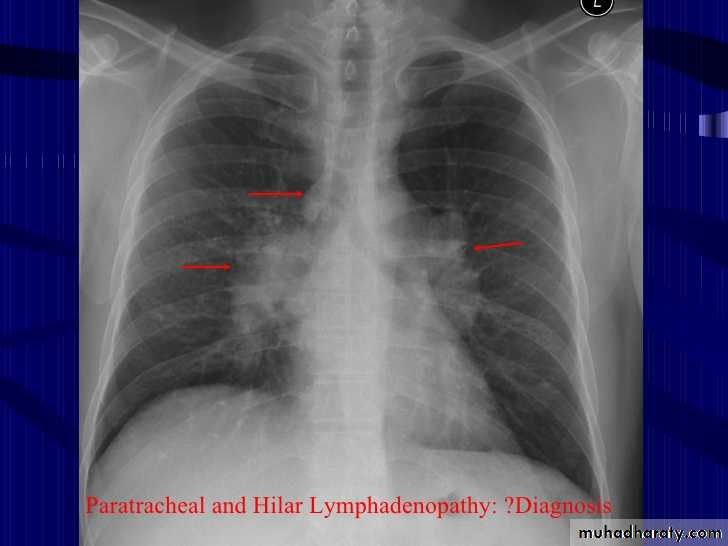

bilateral hilar lymph adenopathyCXR of adult male, PA view shows: Bilateral hilar and paratracheal regions are enlarged and ProminentDDX Infection>>> TB ,sarcoidosis. Metastasis of bronchogenic carcinoma. Lymphoma.

Bilateral hilar LAPCXR of adult male, PA view shows:Hilar lymph nodes are enlarged (bilaterally)